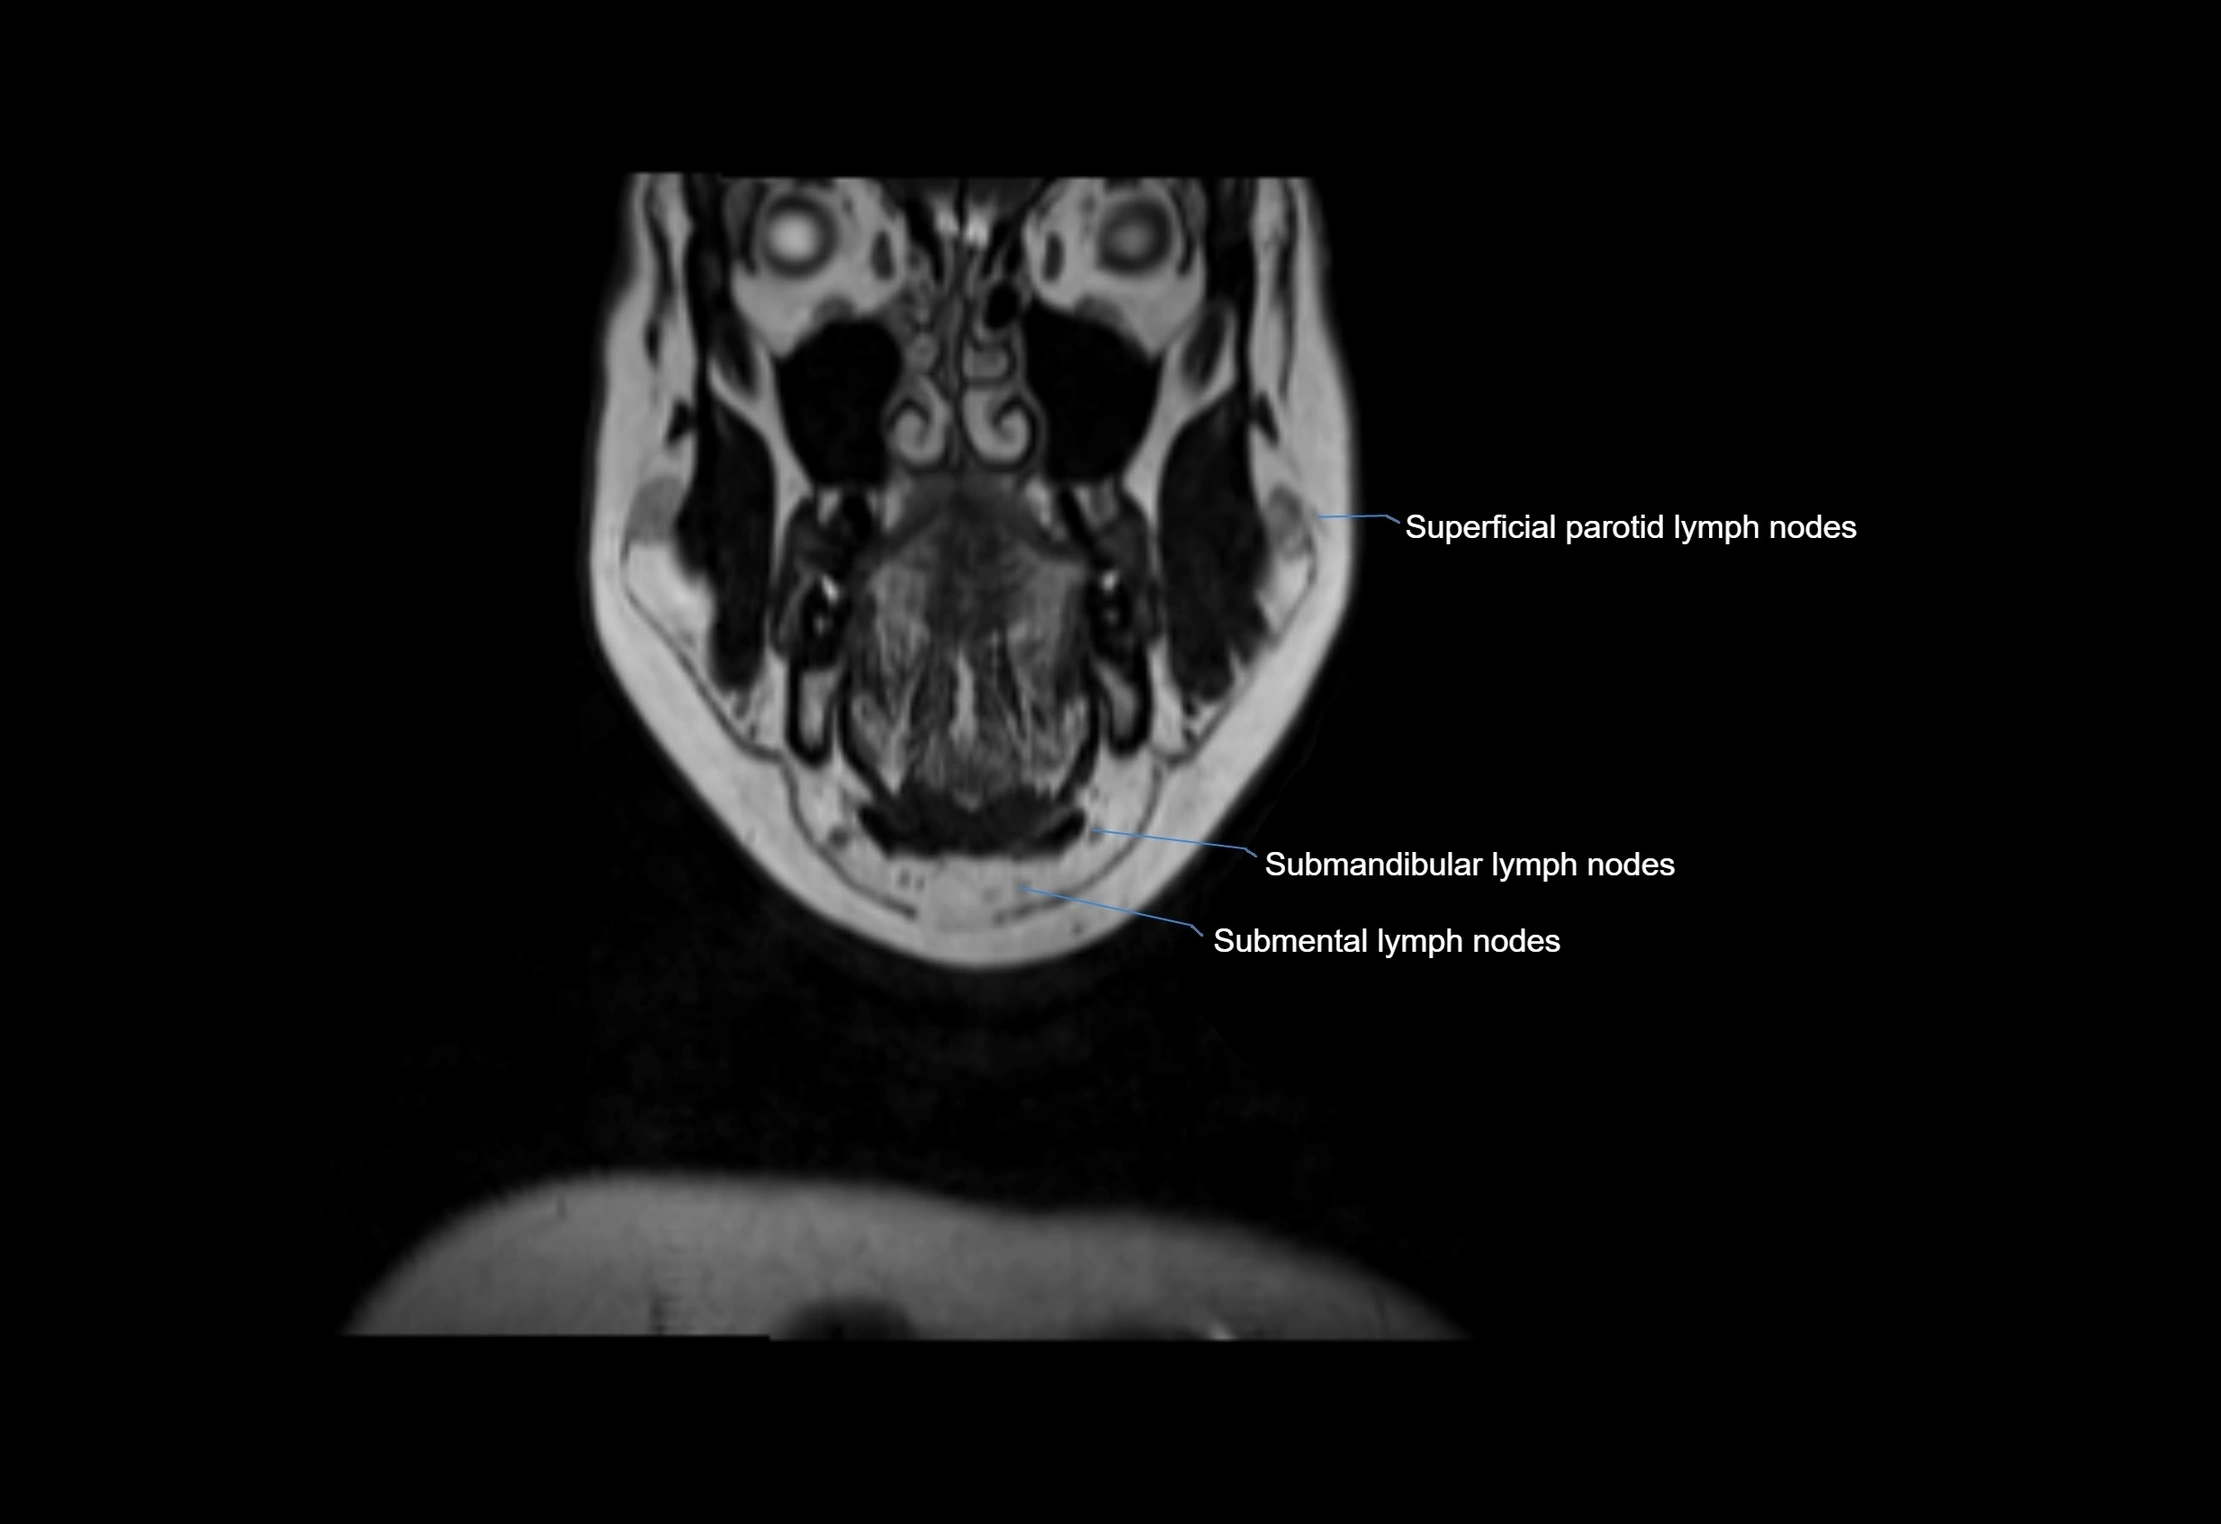

Accessory lymph nodes

Accessory lymph nodes are small, secondary lymph nodes located along the main facial and cervical lymphatic chains, often adjacent to primary lymph nodes, such as preauricular, submandibular, or occipital nodes. They are typically less than 5 mm in diameter, embedded within subcutaneous fat or connective tissue, and may be variable in number and location. These nodes provide additional filtration and immune surveillance for lymph collected from the face, scalp, and neck regions. Accessory lymph nodes are usually non-palpable in healthy individuals but may enlarge in response to infection, inflammation, or metastasis, making them clinically significant.

Location

• Found along primary lymph node chains, including preauricular, submandibular, parotid, and occipital regions

• Embedded in subcutaneous fat or superficial fascia, often lateral or posterior to primary nodes

• Variable in number; may occur unilaterally or bilaterally, depending on individual anatomy

MRI images

image